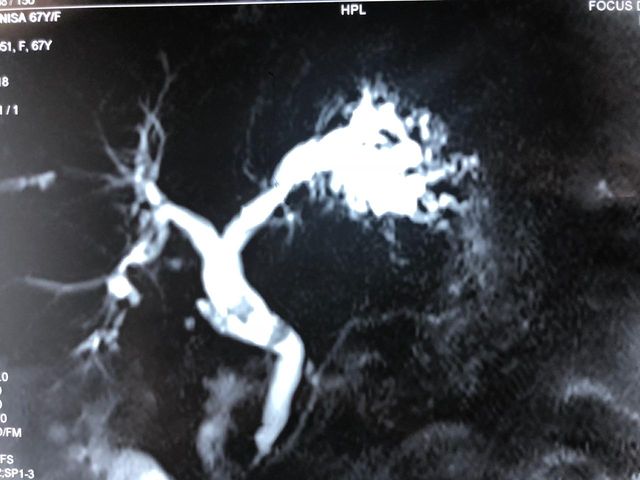

Recurrent pyogenic cholangitis (RPC) - 67 yr old Bangladeshi lady presented with recurrent episodes of jaundice, fever and pain for past 1 year

Interesting images: Recurrent pyogenic cholangitis (RPC) 67 yr old Bangladeshi lady presented with recurrent episodes of jaundice fever and pain for past 1 year. MRCP and CT scan showed left duct stricture with left sided IHBRD and CBD stones and atrophy of left lateral segment. As she 4 duct was also involved we did a left hepatectomy with hepaticoduodenostomy . Reccurant pyogenic cholangitis is a disease charecterised by multiple instances of biliary bacterial infection, hepatic abcesses , multiple stricturing of bile ducts with pigment stone formation in the intrahepatic and extrahepatic biliary tree. This can cause reccurant episodes of cholangitis, chronic illness ultimately leading to liver failure. It is more common in the far east population. Management includes long term biiary drainage with liver resections for segmental disease and liver transplantation in patients with end stage liver failure . The last CT scan shows another CT scan another similar patient with huge intrahepatic stones and abscesses managed successfully by surgery and long term PTBD.